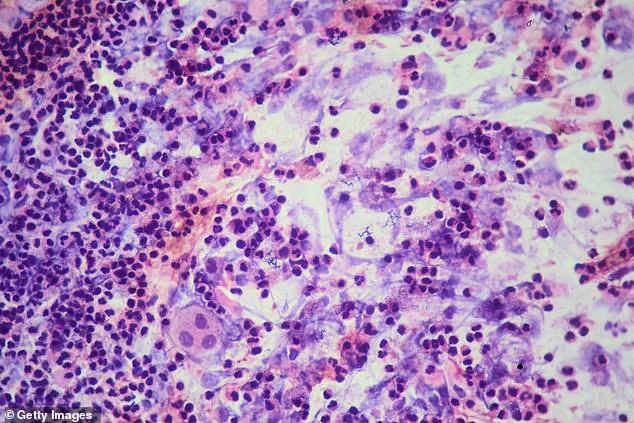

Tuberculosis, which typically presents with symptoms resembling a cold or flu, poses a unique challenge in detection.

The disease’s ability to incubate for weeks or months before showing signs means that individuals can unknowingly spread it for extended periods.

This aspect of TB has been a focal point for public health officials, who have stressed the importance of early detection and treatment.